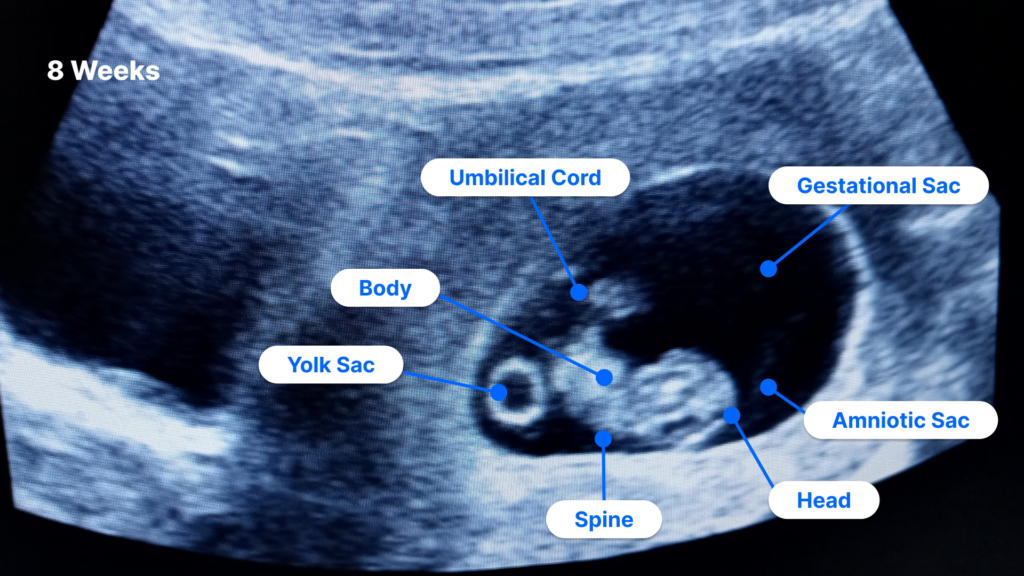

https://www.pockethealth.com/wp-content/uploads/2023/07/8-Weeks-Pregnant-Ultrasound-labeled-diagram-1024x576.png